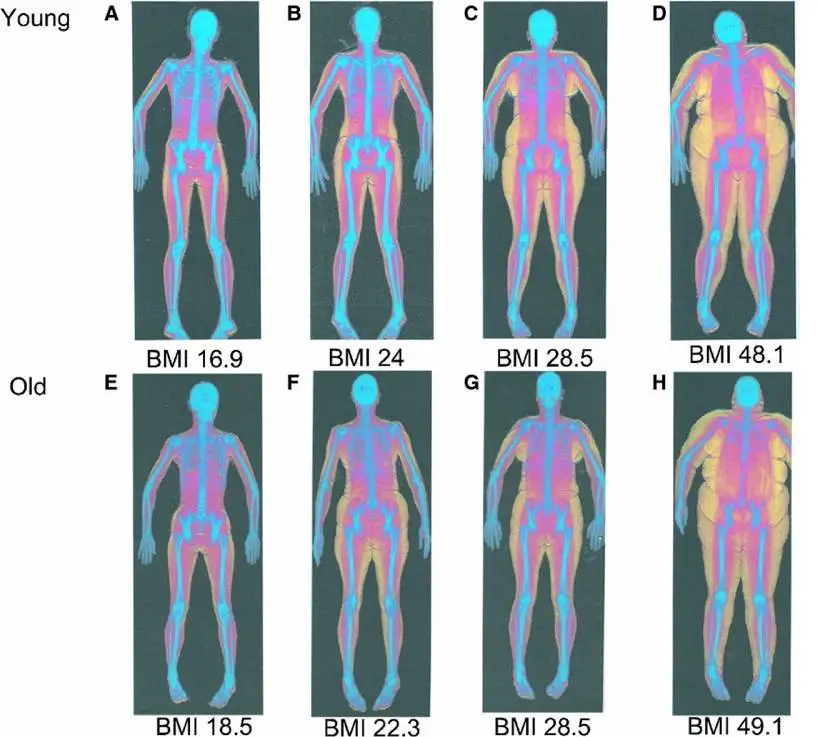

How To Properly Measure Body Fat